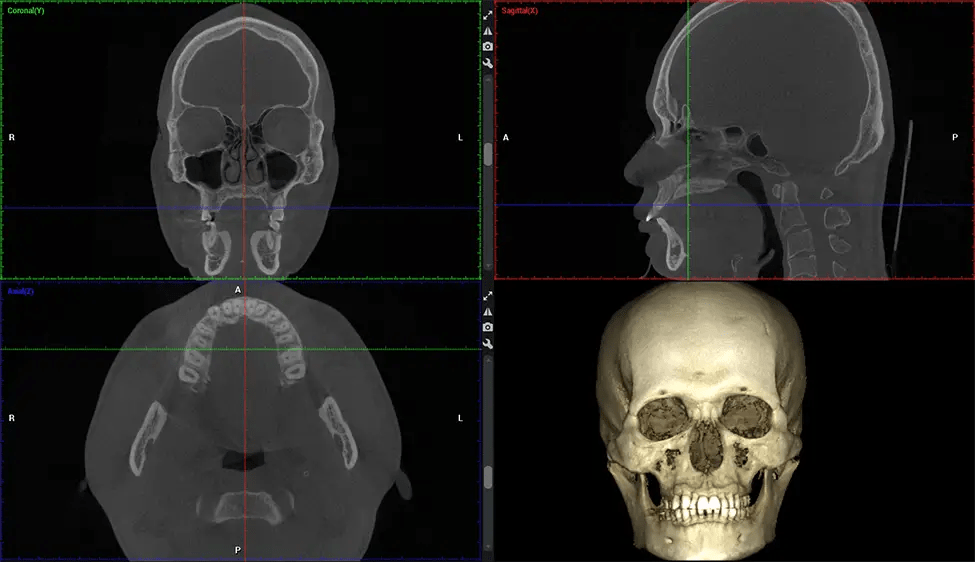

There are many benefits to using CBCT technology, especially compared to the traditional 2D X-ray format. One of the most significant advantages of CBCT scans is that they provide much more information than traditional X-rays. A scan lets your dentist see images from all angles of your jaw and mouth, including your sinuses, nasal cavity, cheekbones, and other surrounding areas. This added information helps your dentist craft a comprehensive treatment plan that addresses all aspects of your oral health.

Orthodontist Assessing facial asymmetry, planning orthognathic surgery, and managing cleft lip and palate and sleep apnea. Provides a comprehensive view of the craniofacial complex to better plan treatments and evaluate outcomes.

Upper Cervical Chiropractor Diagnosing structural problems in the C1-C2 vertebrae, assessing misalignment and instability, and evaluating chronic pain. Enables precise, weight-bearing views of the upper cervical spine, helping to identify abnormalities that inform targeted, non-invasive therapies.

Planmeca Viso G7 CBCT ( Cone Beam CT Scan ) is designed to surpass the demands of industry leaders, specialists, and large institutions. It’s has a large ø25×30 cm sensor with four built-in cameras. It can capture unlimited volume sizes from a ø3×3 cm to a ø30x30cm volume capturing the skullcap through C7 on the cervical spine. The Planmeca Viso G7 offers the industry’s largest single volume scan of ø30×19 cm. It’s poised to handle advanced imaging modalities such as Planmeca ProFace® and Planmeca 4D™ Jaw Motion technology. The occipital head support allows an unimpeded view of facial tissue.